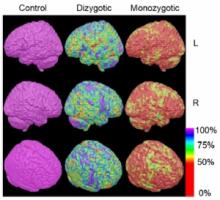

NEURO: Génétique et environnement affectent différentes zones du cerveau